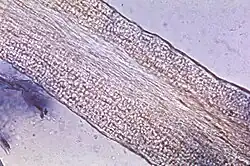

Zur weiteren Untersuchung wird das Hornmaterial auf einem Objektträger mit 15–20%iger Kalilauge (KOH) überschichtet, um die Pilze aus dem Horn herauszulösen. Die Einwirkzeit beträgt etwa eine halbe Stunde, durch vorsichtiges Erwärmen kann der Vorgang beschleunigt werden. Um eine Auskristallisation zu vermeiden, sollte die Probe in einer feuchten Kammer gelagert werden. Unter einem Mikroskop lassen sich die Pilzhyphen und/oder Sporen nachweisen. Gegebenenfalls kann zur Dermatophyten-Anfärbung der Kalilauge Methylenblau zugesetzt werden. Etwas einfacher ist der Nativnachweis mit Fluoreszenzfarbstoffen wie z. B. Acridinorange unter einem Fluoreszenzmikroskop.[33]

Die Untersuchung im Nativmaterial ermöglicht keine Differenzierung des Erregers, auch die Abgrenzung von Schimmelpilzen oder Hefen von Dermatophyten ist schwierig. Zudem können Artefakte die mikroskopische Beurteilung erschweren. Für den Nachweis eines Nagelpilzes ist diese Untersuchung jedoch sicherer als die Pilzkultur.[34] Etwa 15 % der Untersuchungen liefern falsch-negative Befunde.